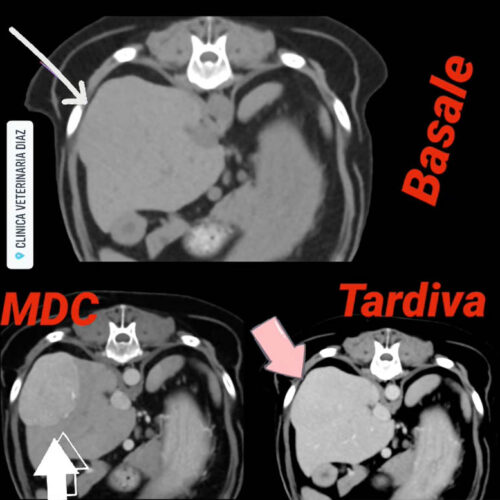

Esempio TAC Veterinaria cane – neoformazione epatica

Di seguito, il Dr Ciro Marra vuole dimostrare con un esempio di uno studio TAC veterinaria, effettuato presso la propria Clinica Veterinaria Diaz, di una neoformazione epatica di un cane in 3 fasi vascolari diverse a distanza di POCHISSIMI SECONDI! – (ved. immagine) – Cosa ha voluto dimostrare? Che se si sbaglia la fase vascolare,...